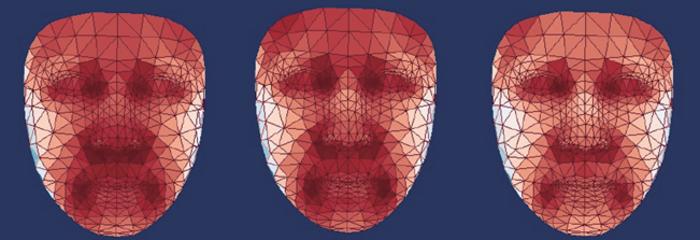

NTV'nin aktardığı habere göre; araştırmacılar, yaklaşık 2 bin 800 Çinli katılımcının yüzlerinin termal fotoğraflarını çekerek 54 farklı noktada sıcaklık analizi yaptılar. Ulaşılan veriler ile eğitilen yapay zeka modeli, katılımcıların biyolojik yaşlarını sıcaklık değişimlerine göre tahmin etmekte kullanıldı. Özellikle burun ve yanakların soğumasının yaşlanmayla ilişkilendirildiği gözlemlendi.

Çalışma, diyabet ve karaciğer hastalığı gibi metabolik bozuklukların, göz çevresinde sağlıklı bireylerle kıyaslandığında daha yüksek sıcaklıklara neden olduğunu ortaya koydu. Bu bulgular, termal yüz görüntülemenin hastalıkların erken teşhisi için potansiyel bir araç olabileceğini gösteriyor.